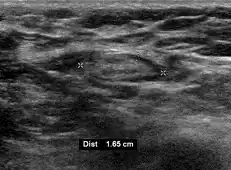

- Absence of the fatty hilum

- Increased focal cortical thickness greater than 3 cm

- Doppler ultrasonography that shows hyperaemic blood flow in the hilum and central cortex and/or abnormal (non-hilar cortical) blood flow.[26]

On ultrasound, B-mode imaging depicts lymph node morphology, whilst power Doppler can assess the vascular pattern.[28] B-mode imaging features that can distinguish metastasis and lymphoma include size, shape, calcification, loss of hilar architecture, as well as intranodal necrosis.[28] Soft tissue edema and nodal matting on B-mode imaging suggests tuberculous cervical lymphadenitis or previous radiation therapy.[28] Serial monitoring of nodal size and vascularity are useful in assessing treatment response.[28]

- Size, where lymphadenopathy in adults is often defined as a short axis of one or more lymph nodes is greater than 10mm.[29]

Lymphadenopathy of the axillary lymph nodes can be defined as solid nodes measuring more than 15 mm without fatty hilum.[36] Axillary lymph nodes may be normal up to 30 mm if consisting largely of fat.[36]

Lymphadenopathy of more than 1.5–2 cm increases the risk of cancer or granulomatous disease as the cause rather than only inflammation or infection. Still, an increasing size and persistence over time are more indicative of cancer.[39]